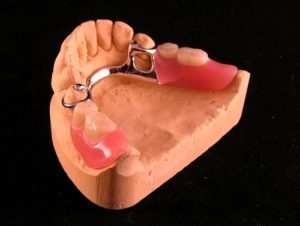

Proteza szkieletowa metalowa – wykonuje się w przypadku braków częściowych w szczęce lub w żuchwie , cechuje się lepszym dopasowaniem i utrzymaniem w jamie ustnej od protezy akrylowej , jest również cieńsza od zwykłej protezy, klamry utrzymujące wykonane są ze stopu metalu.

Proteza szkieletowa metalowa